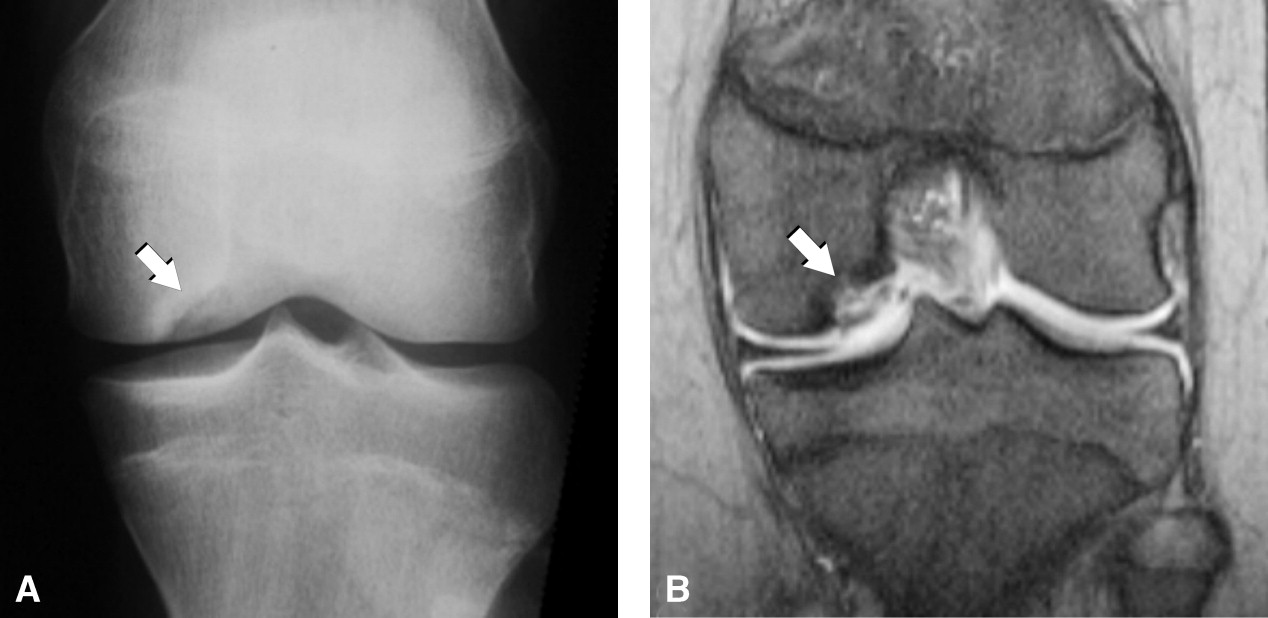

Osteochondritis Dissecans